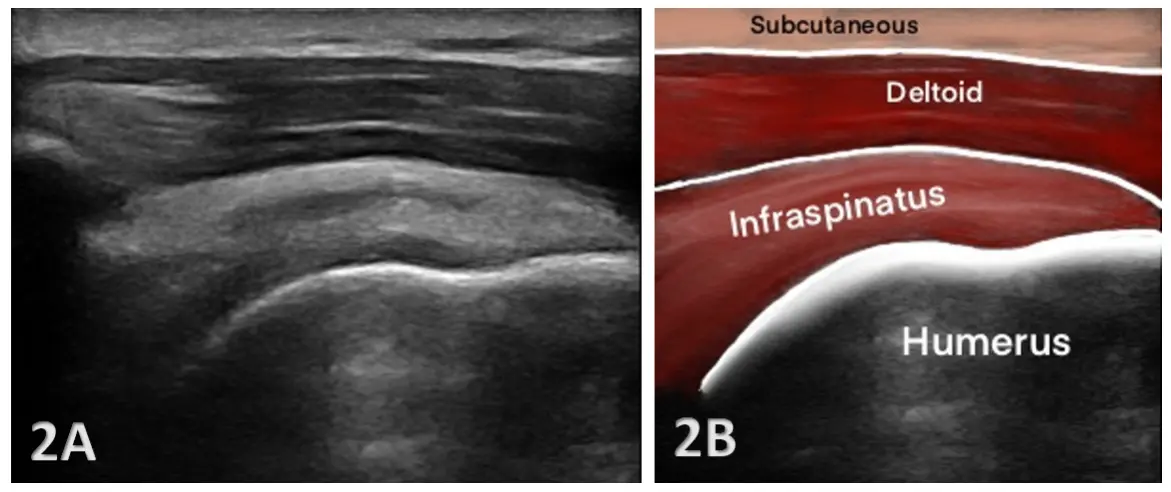

Side-by-side images of a shoulder ultrasound. The left image (2A) shows a grayscale ultrasound scan with layered soft tissues above the curved surface of the humerus bone. The right image (2B) shows the same anatomy with color overlays and labels identifying the subcutaneous layer, deltoid muscle, infraspinatus muscle, and the humerus bone below. Three-panel illustration showing a shoulder joint and an ultrasound-guided injection. The top panel displays the shoulder joint anatomy with the humeral head and surrounding structures. The middle panel shows a needle entering the shoulder while an ultrasound probe is placed on the skin to guide the injection. The bottom panel presents the ultrasound image where the needle is visible approaching the joint. Two ultrasound images labeled SAX and LAX under the title “Full thickness / partial width tear.” The scans show the shoulder tendon with an irregular gap indicating a rotator cuff tear. The images demonstrate how the tear appears in both short-axis and long-axis ultrasound views. If you are searching for accurate diagnosis of joint or muscle pain in Virginia Beach, you may have heard about MSK ultrasound. At Barr Center for Innovative Pain & Regenerative Therapies, musculoskeletal ultrasound is one of our most useful diagnostic and treatment tools for painful conditions.